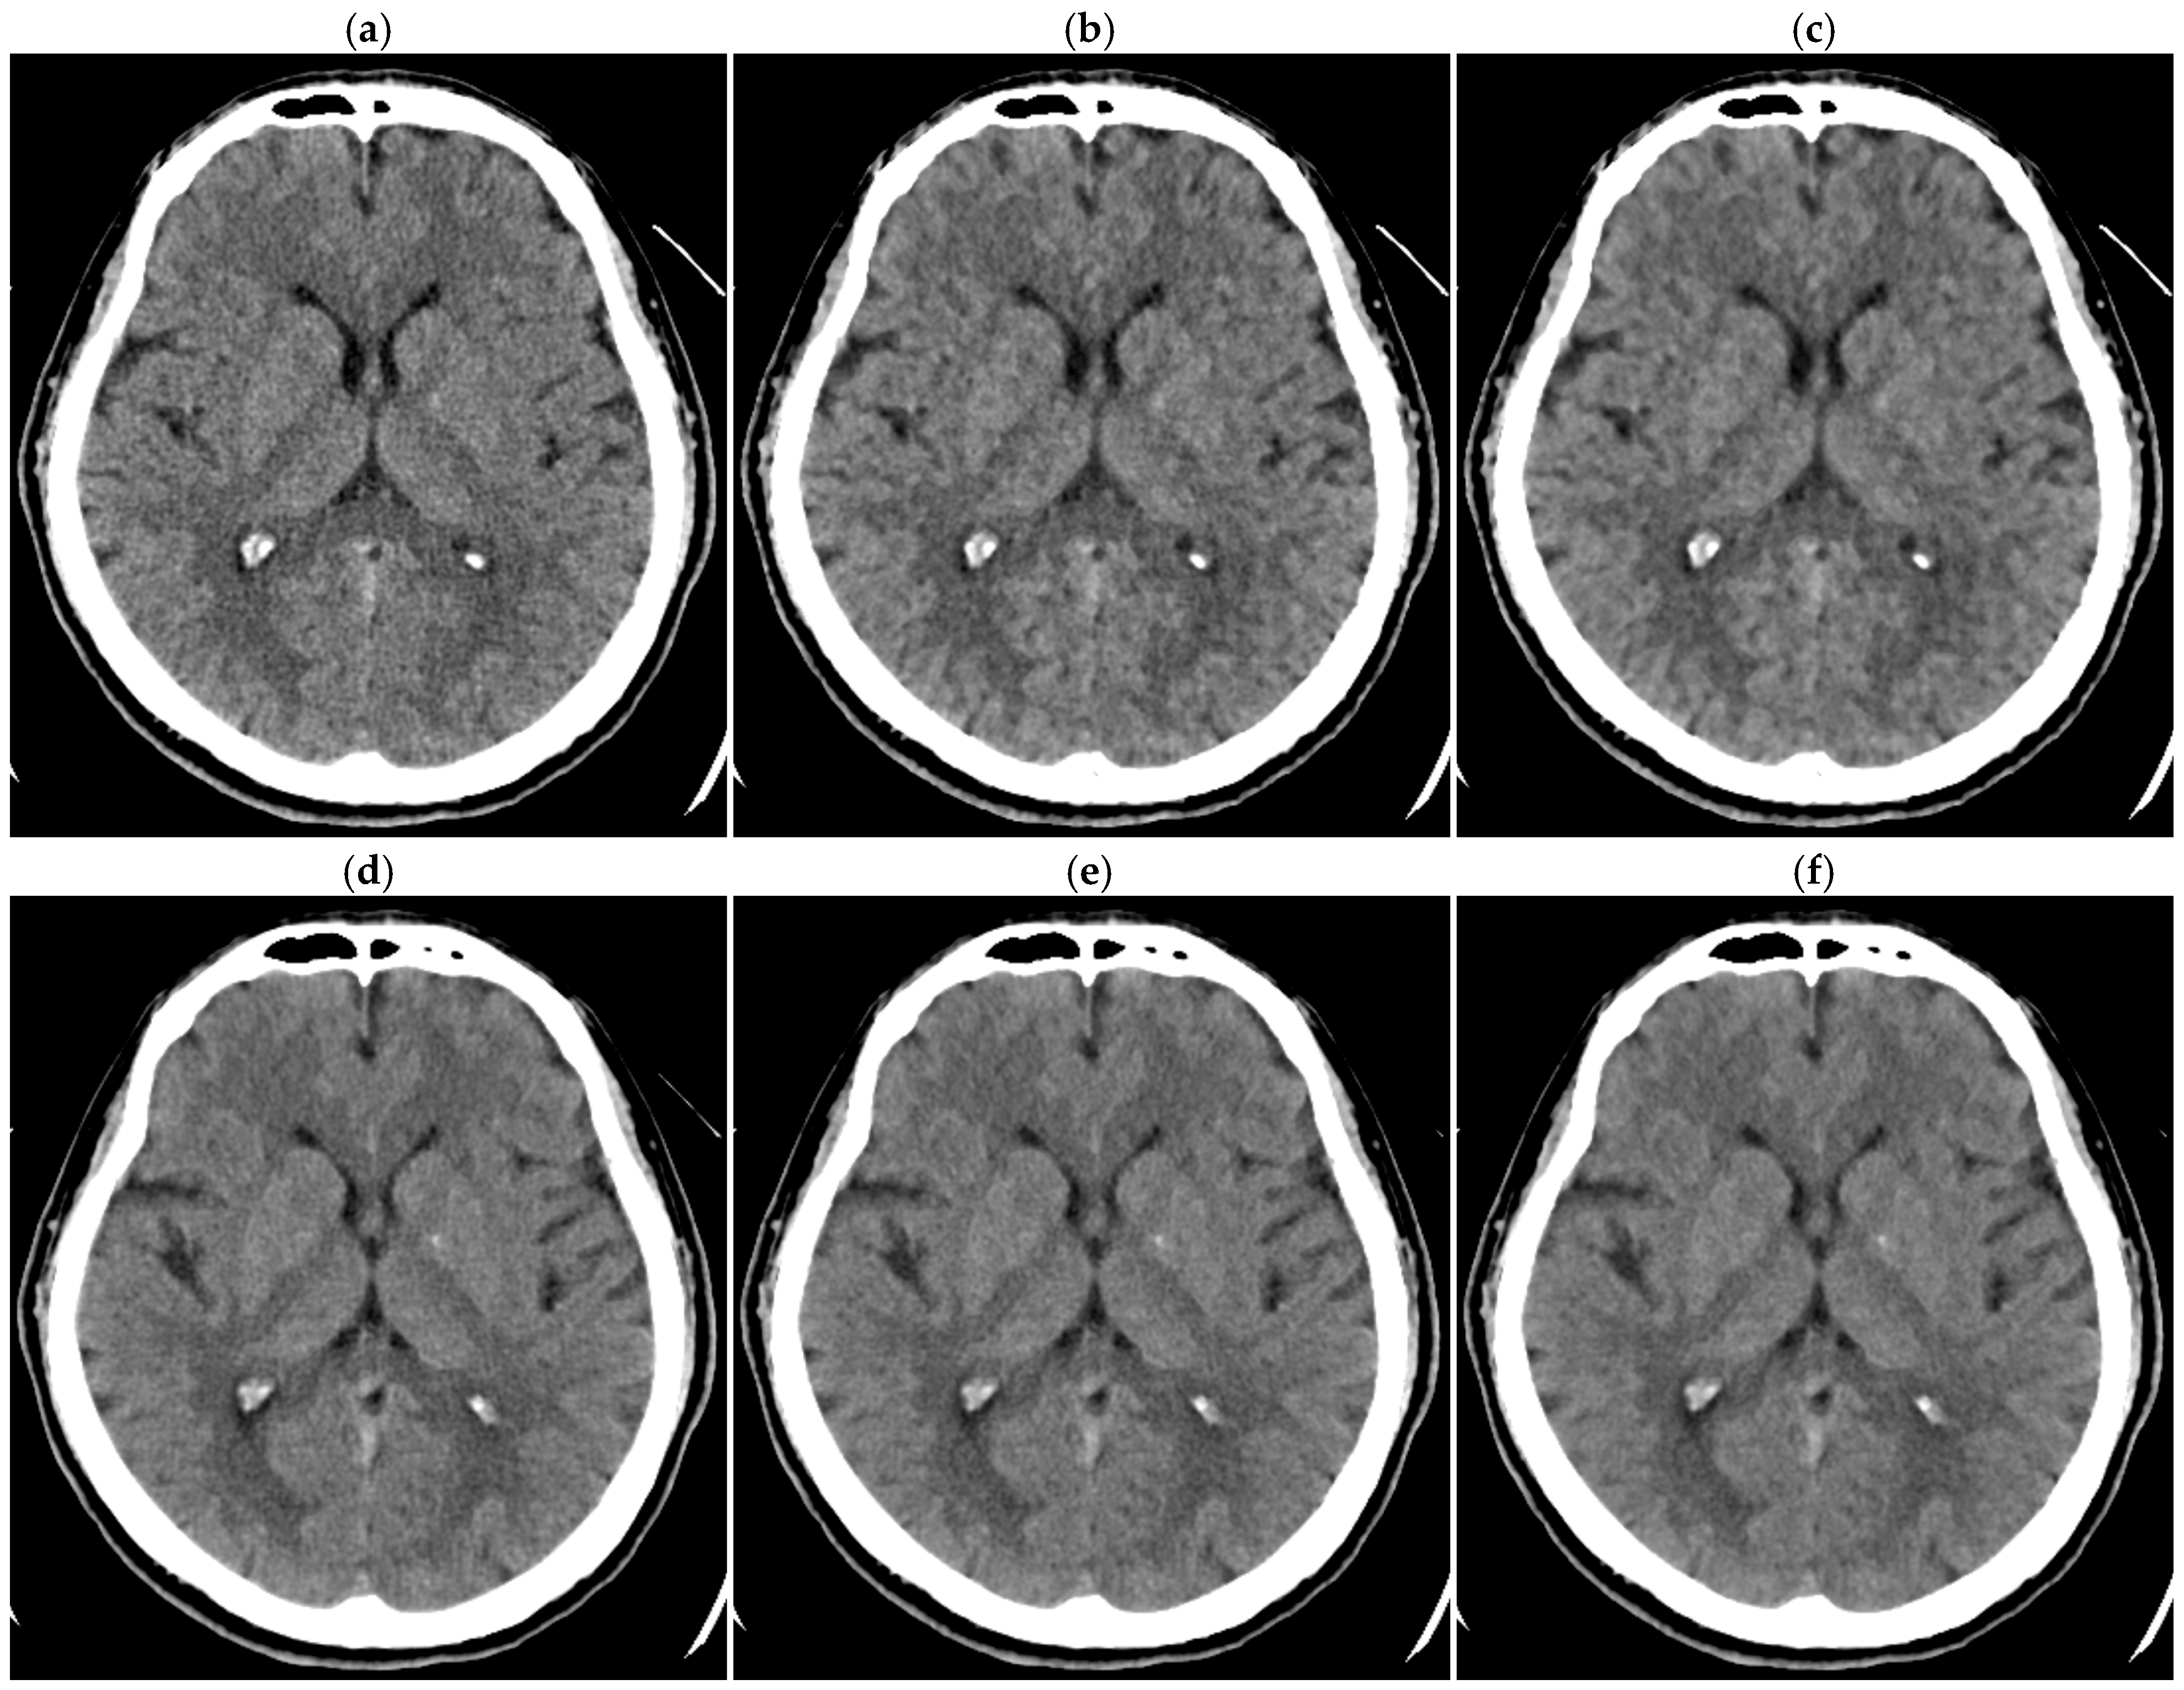

Figure 6.

Brain CT images of 1.25 mm thickness ((a) DLR-M; (b) HIR-L; (c) HIR-H) and 5 mm thickness ((d) DLR-M; (e) HIR-L; (f) HIR-H) in a 38-year-old male patient.

For 1.25 mm thick images, both observers judged DLR-M to be superior to HIR-L and HIR-H in all patients (p < 0.01; Table 4, Figure 6). For 0.625 mm thick images, one observer judged DLR-M to be significantly superior to HIR-L and HIR-H (p < 0.05 for both). The other observer judged DLR-M to be significantly superior to HIR-L (p < 0.05); however, the superiority of DLR-M over HIR-H was not statistically significant. For 5 mm thick images, both observers’ judgments were similar between DLR-M and HIR-L, indicating selecting HIR-L allows HIR to provide image quality comparable to DLR-M. For 2.5 mm thick images, one observer tended to judge DLR-M as superior to HIR; however, the difference between DLR-M and HIR-H was not statistically significant. The other observers’ judgment was almost identical between DLR-M and HIR-L. Overall, significant differences were not indicated between DLR-M and HIR for 2.5 mm thick images.